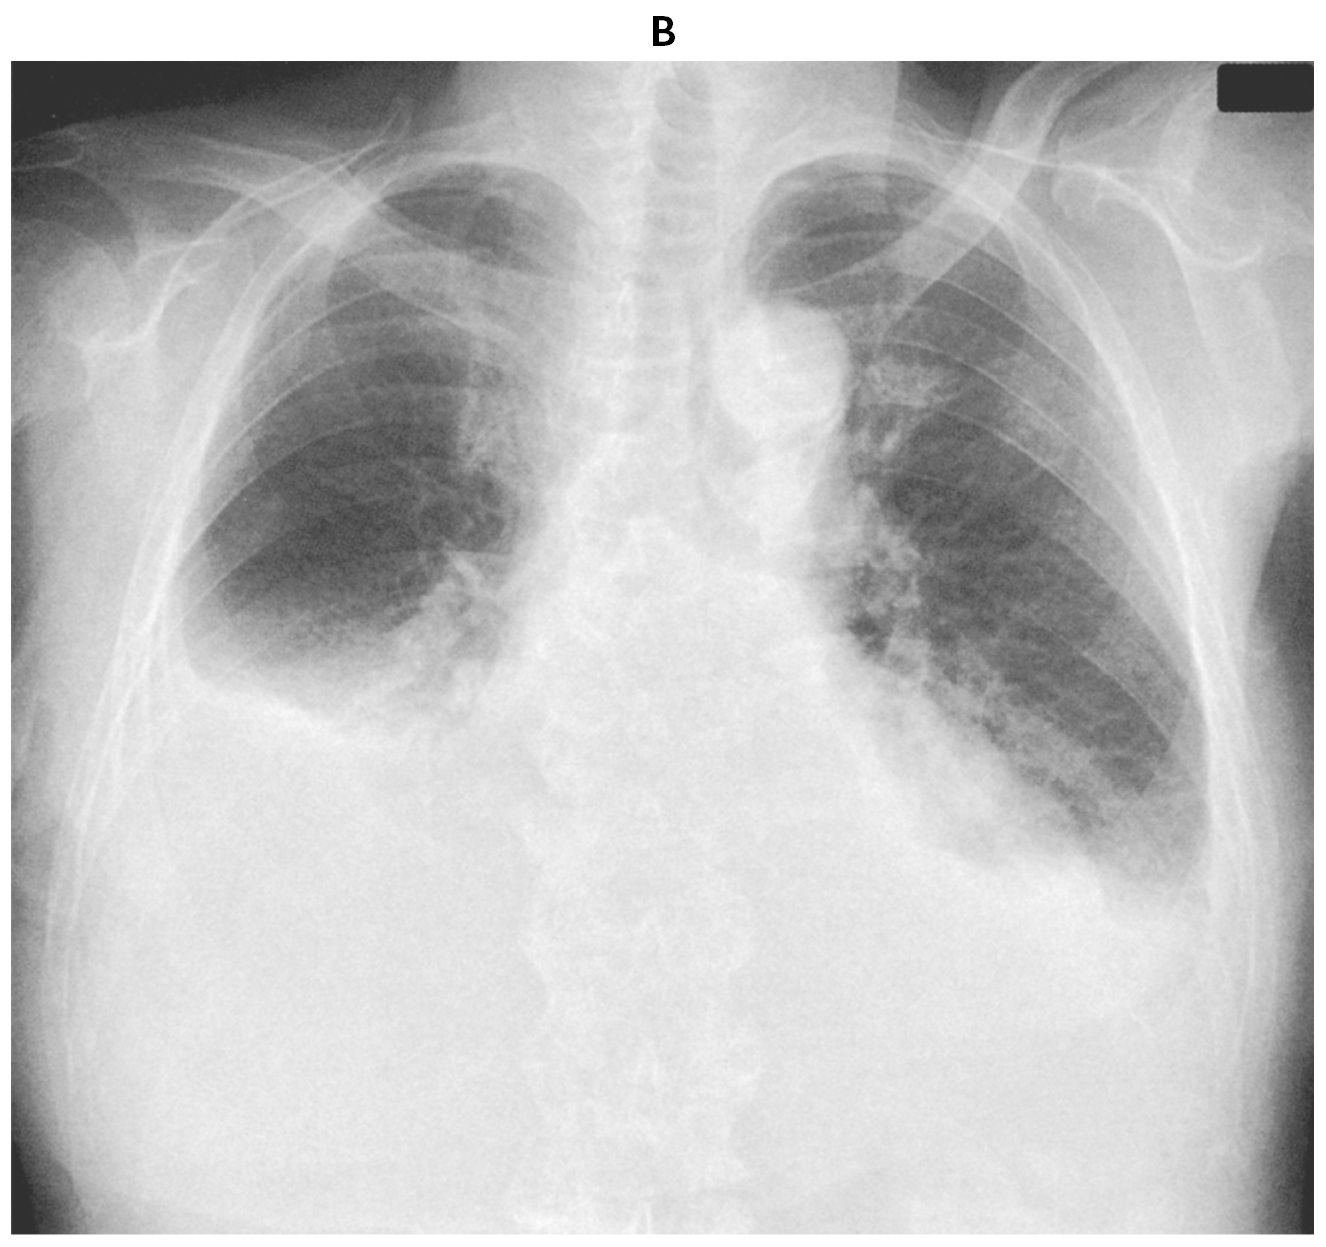

検査所見:血液所見:赤血球402万,Hb 12.1g/dL,Ht 40%,白血球4,500(好中球64%,好酸球2%,好塩基球1%,単球8%,リンパ球25%),血小板16万,Dダイマー0.3μg/mL(基準1.0以下)。血液生化学所見:総蛋白7.3g/dL,アルブミン3.6g/dL,総ビリルビン0.8mg/dL,AST 72U/L,ALT 59U/L,LD 185U/L(基準124~222),ALP 323U/L(基準38~113),γ-GT 69U/L(基準13~64),CK 70U/L(基準59~248),尿素窒素17mg/dL,クレアチニン1.3mg/dL,尿酸5.9mg/dL,血糖117mg/dL,HbA1c 7.2%(基準4.9~6.0),トリグリセリド291mg/dL,HDLコレステロール40mg/dL,LDLコレステロール118mg/dL,Na 132mEq/L,K 4.1mEq/L,Cl 100mEq/L,Ca 9.4mg/dL,BNP 681pg/mL(基準18.4以下),心筋トロポニンT 0.9ng/mL(基準0.01以下)。CRP 1.0mg/dL。血清免疫電気泳動でM蛋白を認めない。動脈血ガス分析(room air):pH 7.32,PaCO2 41Torr,PaO2 69Torr,HCO3 31mEq/L。心エコー検査では,左室収縮能は良好に保たれているが,全周性に左室壁は肥厚しており,輝度が高い。12誘導心電図(A)と胸部エックス線写真(B)とを下に示す。

無料会員登録していただくと、実際の解説をすべて見ることができます。急性の呼吸困難を主訴とする疾患としては,喉頭浮腫,気道異物,自然気胸,気管支喘息,慢性閉塞性肺疾患の急性増悪などの呼吸器疾患,心不全(急性,慢性の急性増悪),肺血栓塞栓症などの循環器疾患が代表的である。この症例では呼吸器感染症と心不全が疑われるが,胸部エックス線写真は肺炎像というよりも両心不全を示唆する所見を示している。診断:心不全(両心不全)(Nohria分類wet and warm) 選択肢考察 ×a 強い呼吸困難,胸痛などにより安静が保てない場合には,血管拡張による前負荷軽減と,交感神経抑制による心筋酸素消費量の減少を目的としてモルヒネを使用する。この症例ではモルヒネが必要となるほどの興奮状態ではない。